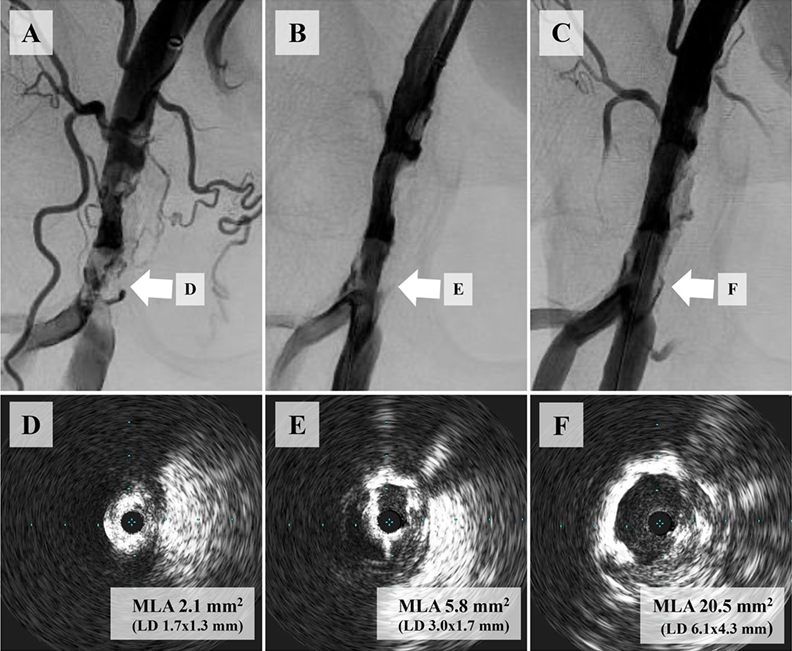

压裂治疗前后及球囊血管成形术后病变形态与IVUS评估的MLA代表性病例。A 初始血管造影显示右侧股总动脉存在重度钙化斑块。B 初始IVUS评估示术前最小管腔面积(MLA)为2.1 mm²(管腔直径:1.7 × 1.3 mm)。C、D 使用7.0 mm非顺应性球囊行球囊血管成形术后,后续血管造影及IVUS显示残余狭窄33%,术中MLA为5.8 mm²(管腔直径:3.0 × 1.7 mm)。E 压裂治疗后,最终血管造影显示满意影像,狭窄率17%。F 压裂后IVUS评估显示术后MLA为20.5 mm²(管腔直径:6.1 × 4.3 mm)。缩略语:IVUS,血管内超声;LD,管腔直径;MLA,最小管腔面积。